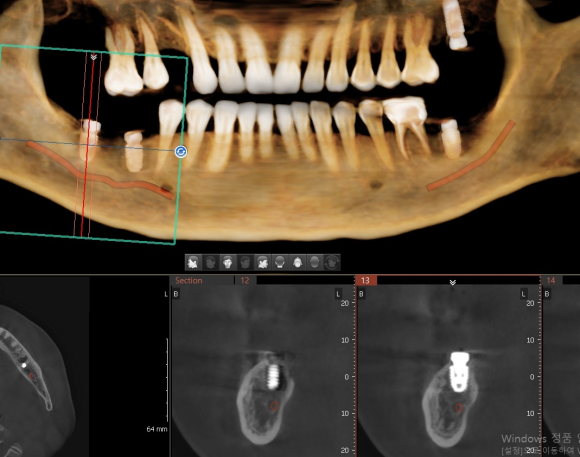

인천에서 오신 분 내과 당일 협진으로 전신 질환 (당요 등등) 확인 후 임플란트 식립. 뼈가 좋지 않아서 충분하게 분석 후 신경 손상을 피하기 위해 전략적이로 보수적으로 접근. 수술 후 3D 사진을 이용한 확인 완료. #상도동에서임플란트가장많이하는치과, #숭실대치과, #상도동치과, #동작구치과, #임플란트,...

인천에서 오신 분 내과 당일 협진으로 전신 질환 (당요 등등) 확인 후 임플란트 식립.

뼈가 좋지 않아서 충분하게 분석 후 신경 손상을 피하기 위해 전략적이로 보수적으로 접근.

수술 후 3D 사진을 이용한 확인 완료.